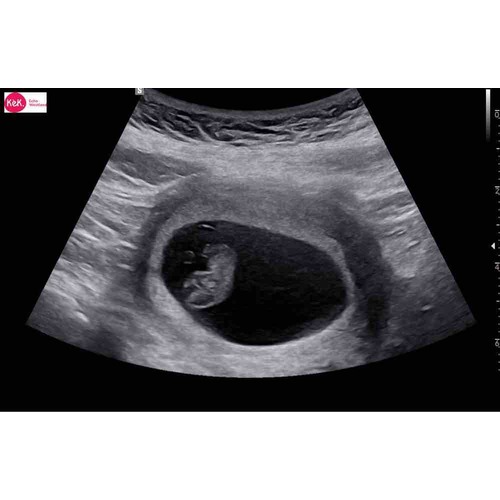

Bij mij was mijn vruchtzakje ook helemaal niet mooi rond. De gynaecoloog heeft hier ook nooit iets van gezegd. Intussen is ze al bijna 5 maandjes oud🥰

Als ik naar al mij 4 keer de zwangerschappen en echo's heb gekeken rond de 6 weken was het bij mij ook allemaal hobbelig en niet mooi rond. 1 van alle is esn miskraam geworden maar dat konden ze niet zien aan de vorm ik heb het ook echt nog nooit gehoord... de volgende echo's werden ze al wat mooier rond... maar hun hebben ervoor gestudeerd... wanneer mag je terug?

Hoi allen, hoe is het uiteindelijk bij jullie allemaal verlopen? Wij hadden gister onze eerste echo (ongeveer 6.3 wk) en onze Vk was ook wat voorzichtig met goed nieuws brengen door de vorm van de vruchtzak. Echter wel een hartslag; langzaam maar dit hoeft nog niets te betekenen met dit termijn.